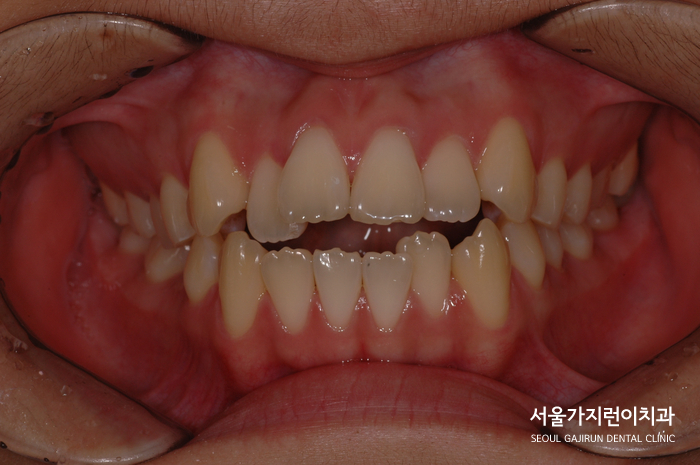

환자분의 경우 앞니가 돌출되어있었고 아래 치아는 배열이 무너진 상태였습니다.

특히 앞니가 닿지 않는 상태 '개방교합'에 불규칙한 치열, 덧니도 나와있어 음식 섭취나 발음에도 불편함이 있었는데요.

치아 사이에 공간이 부족해서 치열이 더 쏠려 악화될 우려도 있었습니다.

여기에 돌출입 증상까지 더해 치아배열 조정이 시급했는데요. 위아래 치열의 맞물림을 유도하는 방식으로 치료를 시작했습니다.